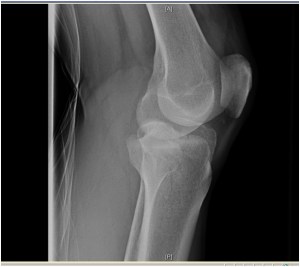

7 comentarios sobre “Rx rodilla perfil

1. Creo que se aprecia, mas en la Rx frente , fractura de meseta tibial y tuberosidad drcha. (espero que te gusto, Ignatius!)

1. También pienso que es una fractura de meseta tibial, pero ¿hay también una luxación?